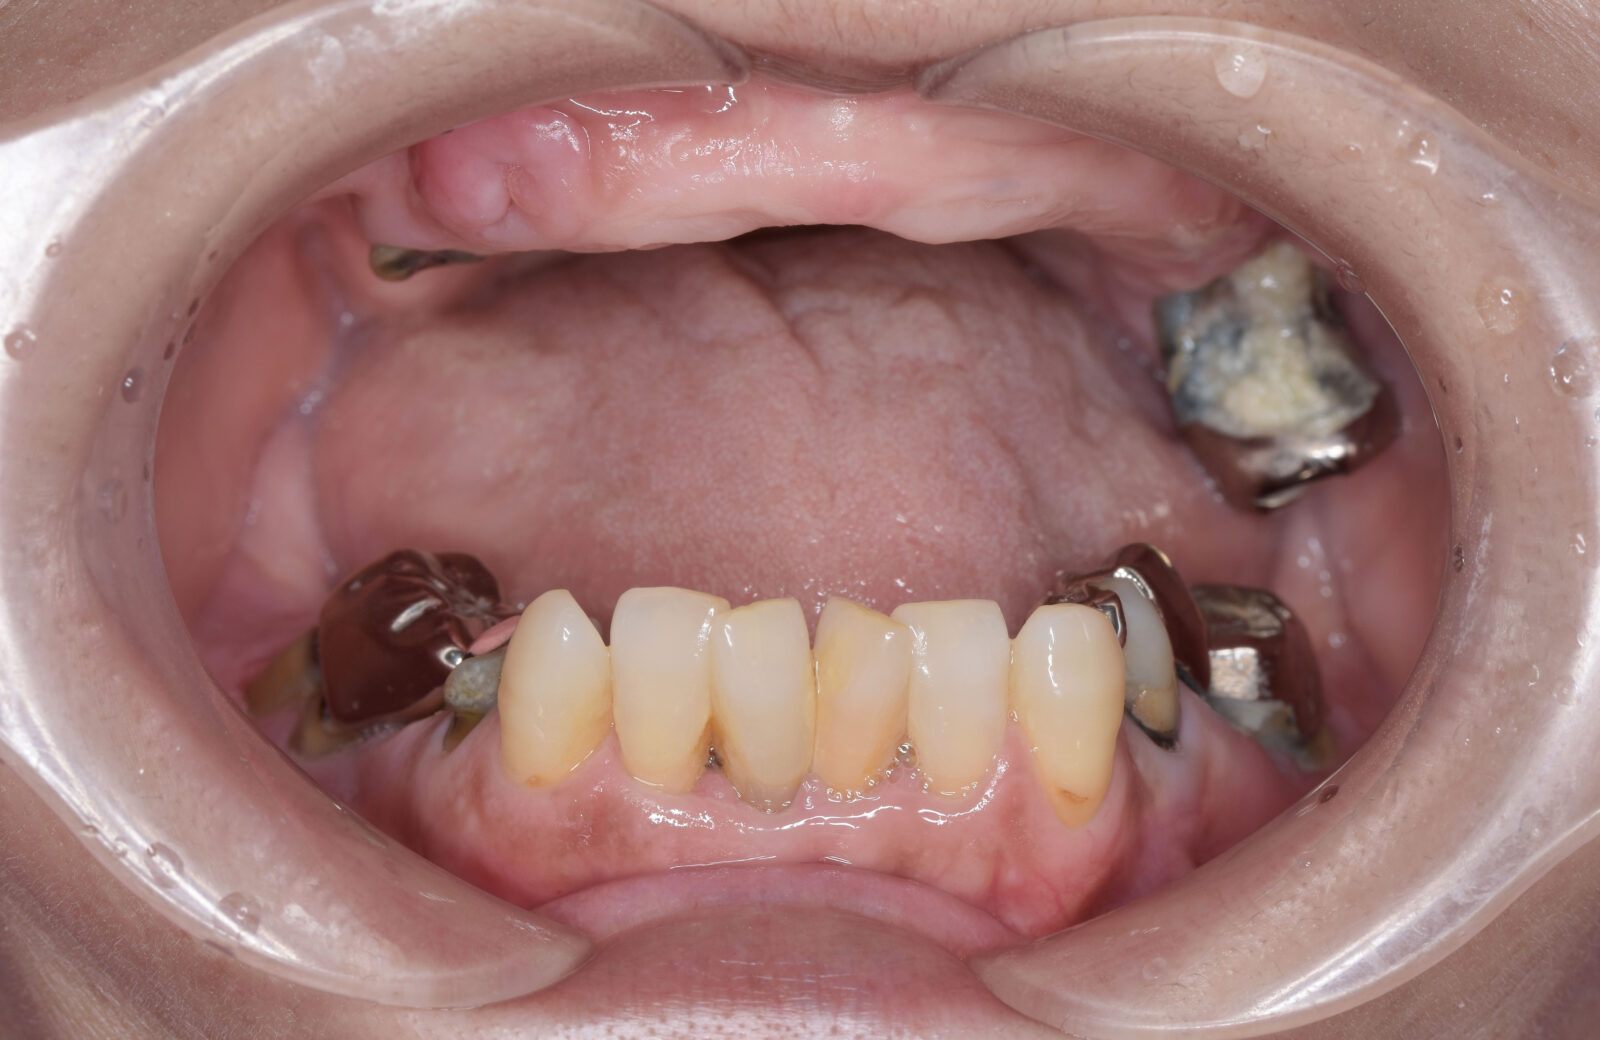

• 治療前

• 治療後

ボロボロの歯を「総合歯科治療」で ※保険外※

ボロボロの状態の治療は「包括的かつ総合的な治療」が必要となります。そのため当院では保険外で治療を行います。

多くの方が、重度のむし歯や歯周病で、抜けてしまっている歯もあるため、まずは虫歯や歯周病治療を行い、残せる歯はしっかり残したうえで、欠損部分の治療を行います。欠損部分に関しては、インプラント、ブリッジ、入れ歯、ケースによってはオールオン4という治療の中から治療法を決定します。